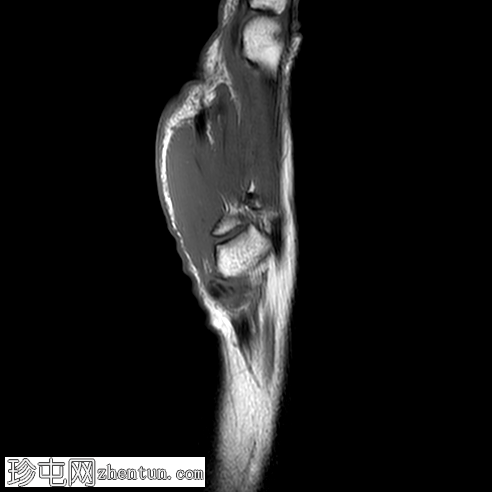

MRI

矢状位

T1加权像

冠状位

PD脂肪抑制像

冠状位PD脂肪抑制像

桡掌侧舟状骨-大多角骨韧带低信号,符合钙化灶,周围伴软组织水肿和舟月关节积液。

本病例为一名既往

健康

的女性,在进行日常家务后,突然出现腕部疼痛和鱼际隆起处肿胀,

影像

学和临床表现均符合急性钙化性关节周围炎的典型特征。